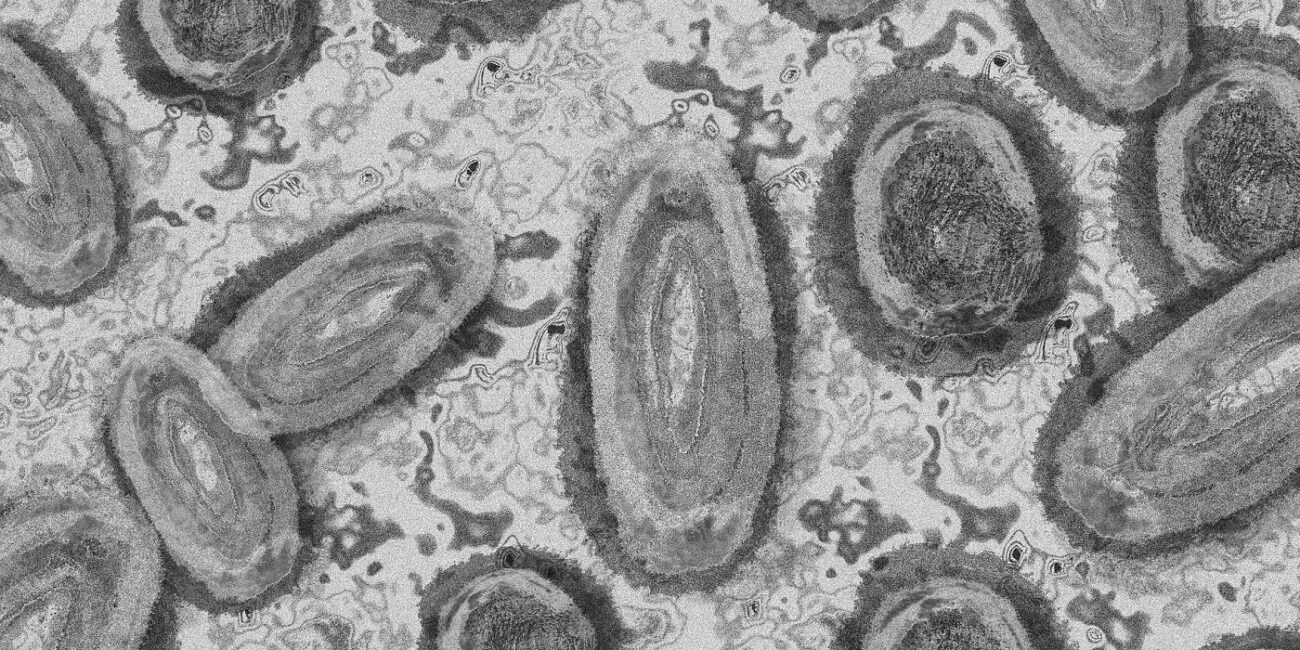

Majmunske boginje pojavile su se i više evropskih zemlja zbog čega svetska javnost pomno prati situaciju. Pre nekoliko dana je objavljeno da je registrovano 80 slučajeva u 12 zemalja. Jedna od njih nalazi se u našem komšiluku. U pitanju je Slovenija, gde se pojavio prvi zaraženi. Ukoliko boginje dođu u Srbiju, virusolozi kažu da nema … Nastavi sa čitanjem Objavljeno UPUTSTVO: Šta raditi ako se MAJMUNSKE BOGINJE pojave kod nas?